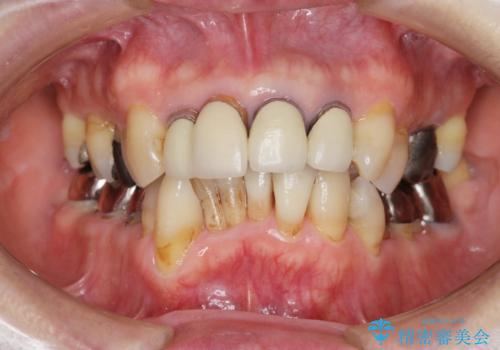

矯正を含む全顎治療